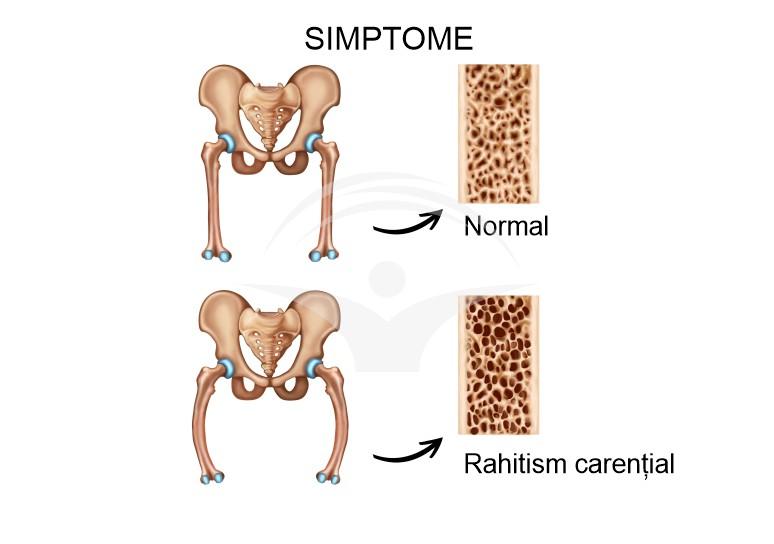

Rahitism este o tulburare a metabolismului osos întâlnită în perioada copilăriei, caracterizată prin mineralizare insuficientă a oaselor în timpul creșterii. În general este legată de dezechilibre ale nutrienților utilizați în formarea scheletului, iar în funcție de cauză poate contribui la o dezvoltare anormală a oaselor și a dinților.

Rahitismul are cauze multiple: cel mai frecvent este asociat cu un deficit de vitamina D, care poate apărea din expunere solară insuficientă sau aport alimentar inadecvat. Tulburările de absorbţie intestinală, afecţiunile hepatice sau renale cronice care modifică metabolizarea vitaminei D şi unele medicamente pot contribui la dezechilibrele minerale care afectează dezvoltarea osoasă. De asemenea, factori biologici precum prematuritatea sau pigmentarea cutanată mai închisă pot reduce sinteza cutanată a vitaminei D şi pot creşte vulnerabilitatea copilului.

Evaluarea clinică inițială se concentrează pe anamneză detaliată și examenul fizic, măsurători ale creșterii și observarea semnelor musculo‑scheletice; investigațiile care pot ajuta la clarificare includ teste de laborator pentru parametrii metabolici ai osului și investigaţii imagistice pentru a evalua modificările osoase. De regulă, se pot utiliza analize sanguine care vizează niveluri ale electroliților şi markeri ai metabolismului osos, precum şi radiografii regionale, fiecare metodă putând contribui la conturarea tabloului clinic fără a înlocui evaluarea medicală de specialitate.

Principiile terapeutice se concentrează pe corectarea dezechilibrelor nutriționale și pe identificarea cauzelor subiacente care pot contribui la tulburările de creștere osoasă. Suplimentarea adecvată cu vitamina D și calciu, adaptată de către un specialist, poate ajuta la restabilirea parametrilor biochimici și la susținerea mineralizării osoase; în cazul unor afecțiuni secundare, abordarea specifică a cauzei (de exemplu malabsorbție sau boli renale) poate contribui semnificativ la tratament. Managementul optim implică colaborare multidisciplinară între pediatru, endocrinolog și, după caz, ortoped, pentru a asigura intervenții coerente și sprijin pentru familie.